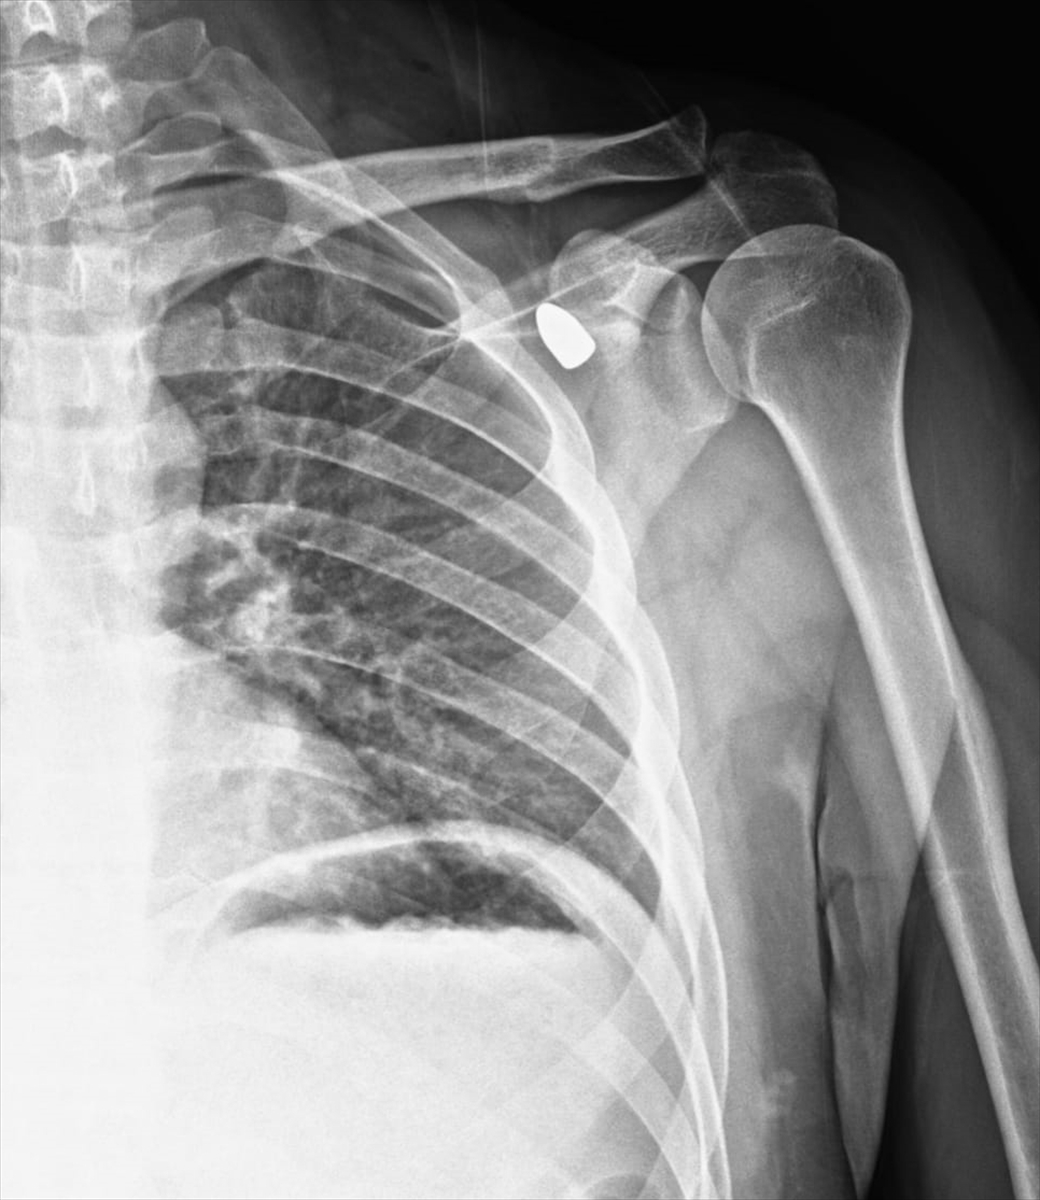

Konya’nın Akşehir ilçesinde, okul müdürü Celal Şenyiğit’in 2019 yılında omzuna isabet eden yorgun mermi, altı yıl sonra kendi kendine yüzeye çıkarak basit bir operasyonla alındı.

O dönemde Konya ve Ankara’daki birçok doktora başvuran Şenyiğit, merminin sol kol hareketlerini sağlayan sinirlere çok yakın olması nedeniyle alınmasının büyük risk taşıdığı bilgisiyle karşılaştı. Doktorlar, “Mermi olduğu yerde kalırsa zarar vermez” diyerek operasyonu uygun görmedi ve Şenyiğit yıllarca mermiyle yaşamak zorunda kaldı.

Son aylarda koltuk altında ağrı ve sertlik hisseden Şenyiğit yeniden doktora başvurdu. Yapılan muayenede, bir süredir yağ bezesi sanılan kitlenin aslında yıllar önce saplanan mermi olduğu ortaya çıktı.

Hızlı ve risk taşımayan bir operasyonla mermi çıkarıldı. Celal Şenyiğit, yaşadığı olayı “mucize” olarak nitelendirirken, merminin balistik incelemeye gönderildiğini belirtti. Şenyiğit, “Yıllarca bu mermiyle yaşadım. Doktorlar riskli olduğu için alamamıştı. Şimdi ise kendi kendine yüzeye çıkıp kolayca alındı. Allah’a şükürler olsun” dedi.